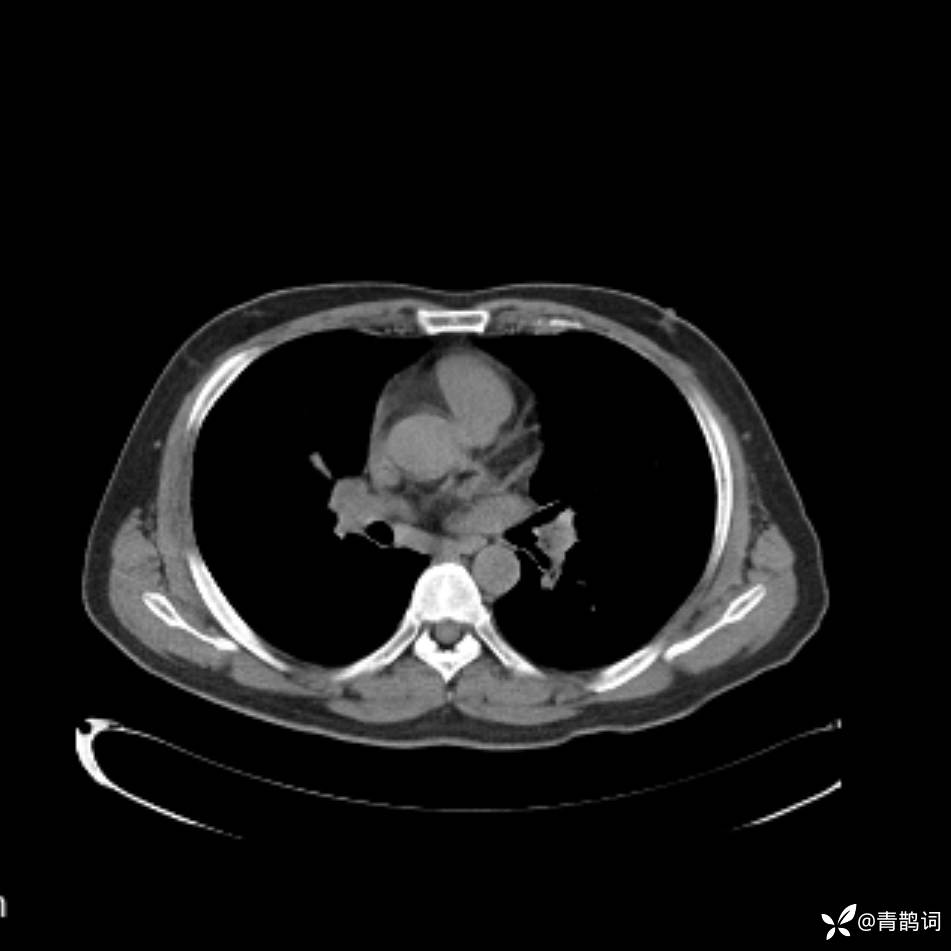

患者年龄:30岁。

患者性别:男。

简要病史:左颜面部肿胀2年,反复咳嗽咳痰,逐渐加重。

结合病史及影像学表现,期待评论区各位老师各抒己见~